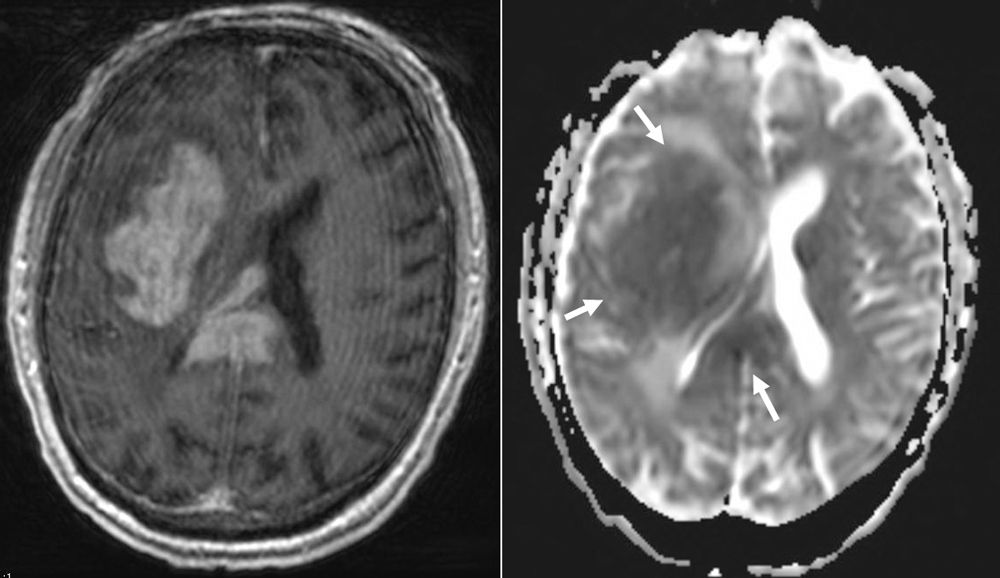

A 74-year-old, right-handed man with a medical history of hypertension, hyperlipidemia, and type 2 diabetes mellitus was found lying on the ground by his family and was brought to the emergency department, where he was found to have left facial drooping and weakness. On admission, a T1 post-contrast axial MRI and apparent diffusion coefficient diffusion-weighted imaging were performed.

Based on the images shown, what is the most likely diagnosis?